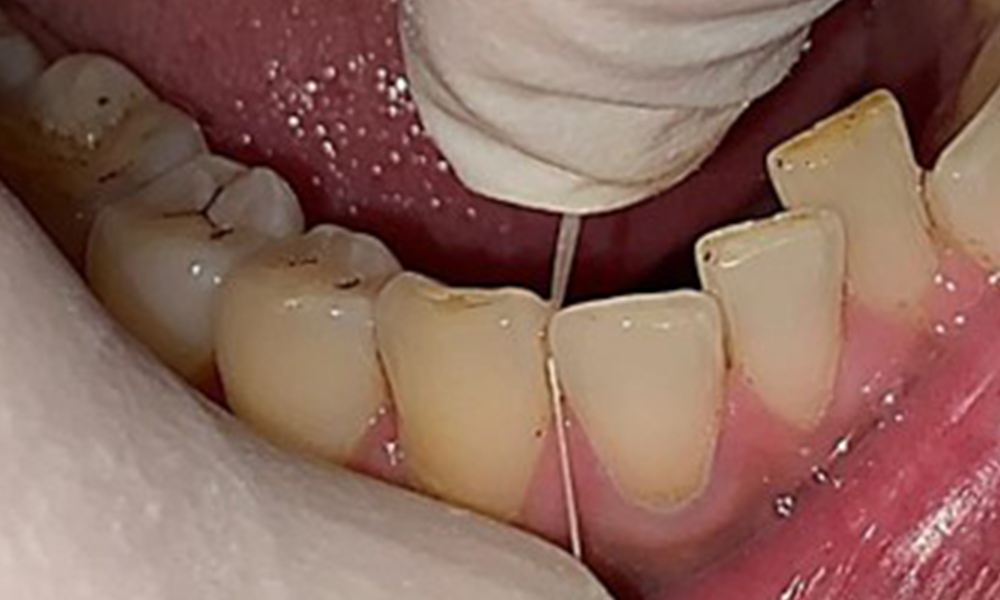

Extra- und Intraoraler Befund

Extraoral sind keine pathologischen Befunde festzustellen, intraoral zeigen sich bei der Frontalansicht im Bereich der keratinisierten Gingiva und am Übergang zur beweglichen Schleimhaut bräunlicheVerfärbungen (Abb. 2), welche auf den Nikotingenuss zurückzuführen sind. Am Gaumenbereich zeigen sich insbesondere im Bereich Oberkiefermolaren palatinal weißliche Schleimhautveränderungen, die ein Hinweis auf einen erhöhten Verhornungsgrad sind und ebenso auf den Nikotingenuss zurückzuführen sind. Die Zunge ist mit einem weiß-bräunlichen abwischbaren Belag versehen.